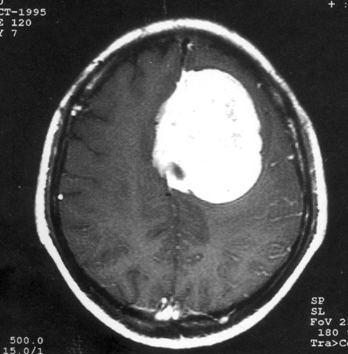

问题 病历摘要:??患者,男,40岁。发作性左下肢抽搐1年余,每次发作3~5分,每周发作1~2次。每次发作后感左下肢乏力,约半日后可自行恢复。既往身体健康。体检:神清,头顶部偏右有局限性骨性隆起(1.5×1.5cm),左鼻唇沟稍浅,伸舌居中。感觉、运动无明显异常。左浅反射减退,左下肢腱反射稍亢进,左Babinski征(-)。 术后处理包括下列哪些措施?提示:肿瘤病理报告为脑膜瘤